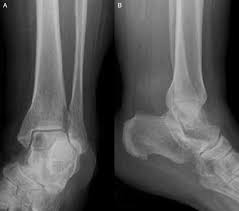

The world health organization has identified 82 different benign and malignant foot lesions. Bone cancer can begin in any bone in the body, but it most commonly affects the pelvis or the long bones in the arms and legs. Learn enough about bone cancer to make decisions about your care. The bone pain is described as aching, throbbing, stabbing, and excruciating. Ask your doctor about your bone cancer, including your treatment options and, if you like, your prognosis. Bone cancer is a fairly rare disease, so if you've developed bone pain, don't jump to conclusions. But we also have secondary bone, those that metastasize from other tumors and form secondary metastatic masses in the bones. Other conditions, like osteoporosis or arthritis, may also cause bone or joint pain. It can spread to distant organs, such as the lungs. The most common symptom of cancer in the hip is pain, which can be severe enough to disrupt sleep. Whether primary or metastatic, cancer in the bones may present with symptoms such as increasing pain, swelling and/or a more sudden intense pain from a pathologic fracture —a fracture that occurs in a bone that has been weakened by the presence of tumor. Grade 3 (g3) means the cancer looks very abnormal. The bone may look ragged, or it may appear to have a hole in it.

Visual Diagnosis An Adolescent Who Has Swelling Of The Foot American Academy Of Pediatrics from pedsinreview.aappublications.org The scale used for grading bone cancer is from 1 to 3. Where the cancer is located, the bone might appear ragged or look like it has a hole. A tumor that has metastasized to bone is not made of bone cells. It may resemble a plantar's wart or a foot ulcer, and it may feel scaly. You'll often see it on your face, head, or neck. When a bone tumor grows, it presses on healthy bone tissue and can destroy it, which causes the following symptoms: Sometimes, people with bone sarcoma do not have any of these changes. This can lead to insomnia, loss of appetite, and inability to carry out normal daily activities.